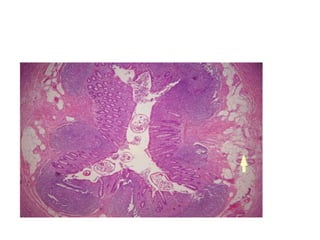

• The histological examination revealed

superficial fragments of gastric mucosa

showing surface erosions, congestion, many

ectatic blood vessels and dense infiltration by

lymphocytes, plasma cells, neutrophils and

eosinophils in the lamina propria.

• Furthermore, the gastric mucosa showed

numerous cross-sections of adult worms, eggs

and rhabditiform larvae of Strongyloides

stercoralis in the glands and crypts.